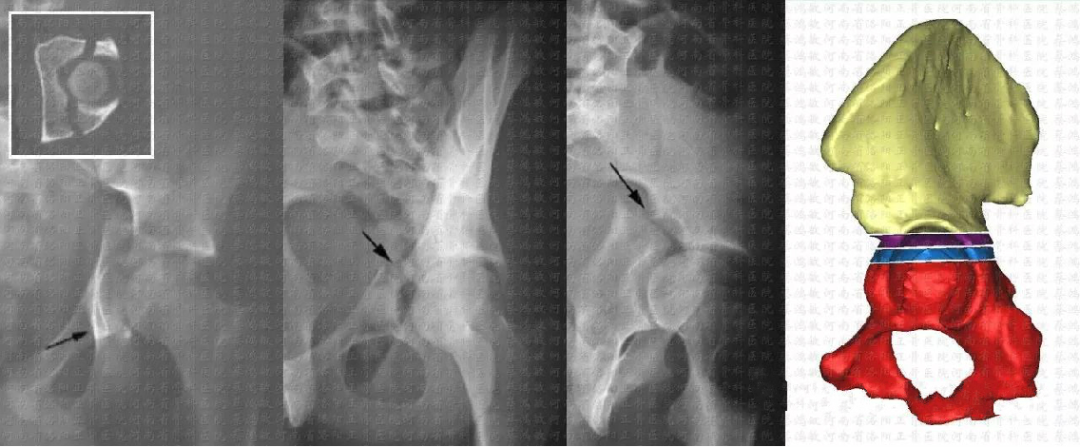

髋臼骨折分型

解剖(Judet-Letournel)分型:应用范围最广,临床指导价值最高。

简单(elementary)5型:后壁、后柱、前壁、前柱、横形复杂(associated)5型:后柱+后壁、横形+后壁、T型、前柱/壁+后半横形、双柱

复杂型    双柱骨折(23%)